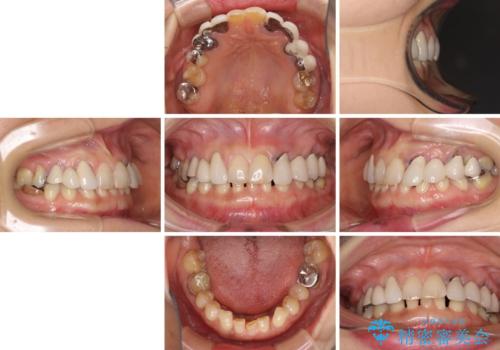

- 割れていると言われて放置してしまった歯や、前歯のデコボコなどが気になるとのことで来院された患者様です。

左上の歯は割れてしまっており、抜歯のうえインプラント治療が必要であり、他にも抜歯の必要な歯がある状態でした。

上顎はほぼ全ての歯をセラミッククラウンにて補綴治療を行う必要があるため、気になるデコボコや深い咬み合わせを改善するために下顎と上顎の臼歯部の矯正治療を行うこととしました。

並行して左下にはインプラントを埋入し、矯正治療を終えると同時に補綴治療を行うこととしました。

過蓋咬合(下顎前歯が隠れてしまうほどの深い咬み合わせ)のため、スムーズに歯が動かず矯正治療に時間がかかりましたが、無事に仕上げることができました。